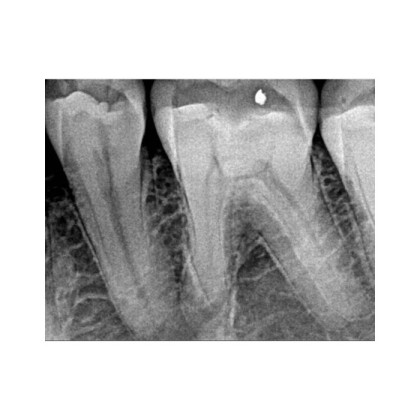

- Диагностика кариеса и его осложнений – выявление патологий на ранних стадиях.

- Эндодонтия – контроль обработки корневых каналов.

- Имплантология – точная оценка состояния костной ткани перед установкой имплантов.

⚙️ Передовые инструменты обработки изображений – улучшенная контрастность, фильтрация шумов, регулировка резкости для повышения качества диагностики.

| Разрешение пар линий | 16 |